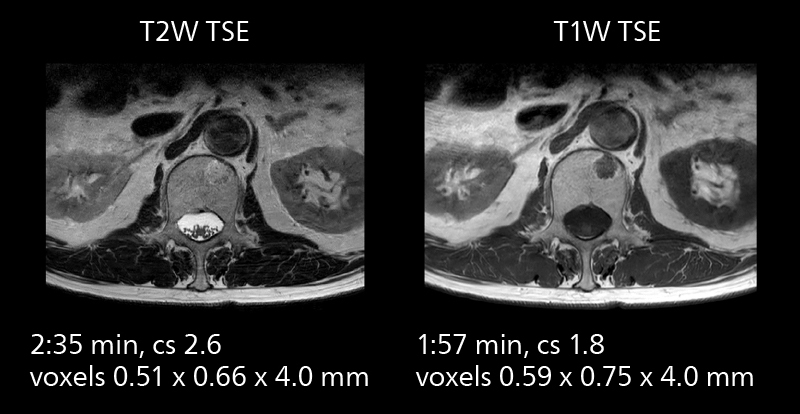

MRI of prostate

Examples of prostate imaging showing faster scan times and improved resolution illustrate the power of SmartPath to Elition X in this case of prostate cancer with PI-RADS score 4.

MRI of prostate

Examples of prostate imaging showing faster scan times and improved resolution illustrate the power of SmartPath to Elition X in this case of prostate cancer with PI-RADS score 4.